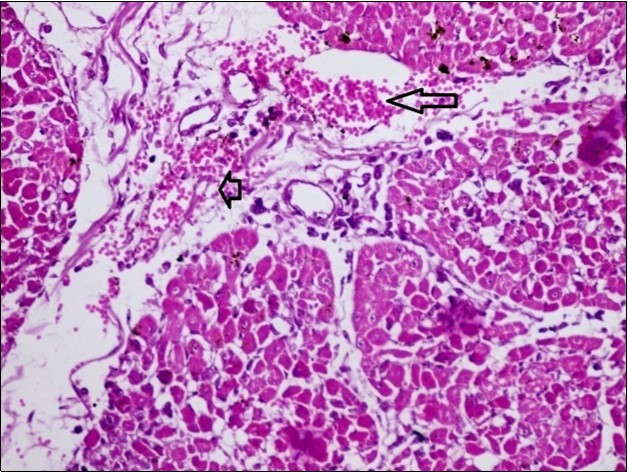

Figures 6.kidneys (dead cattle less than 1 year old) showed severe hydropic degeneration of renal tubular epithelium accompanied by dilated renal tubules, vesicles formations and casts (arrows). (H&E, X 100)

Figures 7.kidneys (dead cattle less than 1 year old) showed severe hydropic degeneration of renal tubular epithelium accompanied by dilated renal tubules, vesicles formations and casts (arrows). (H&E, X 60)